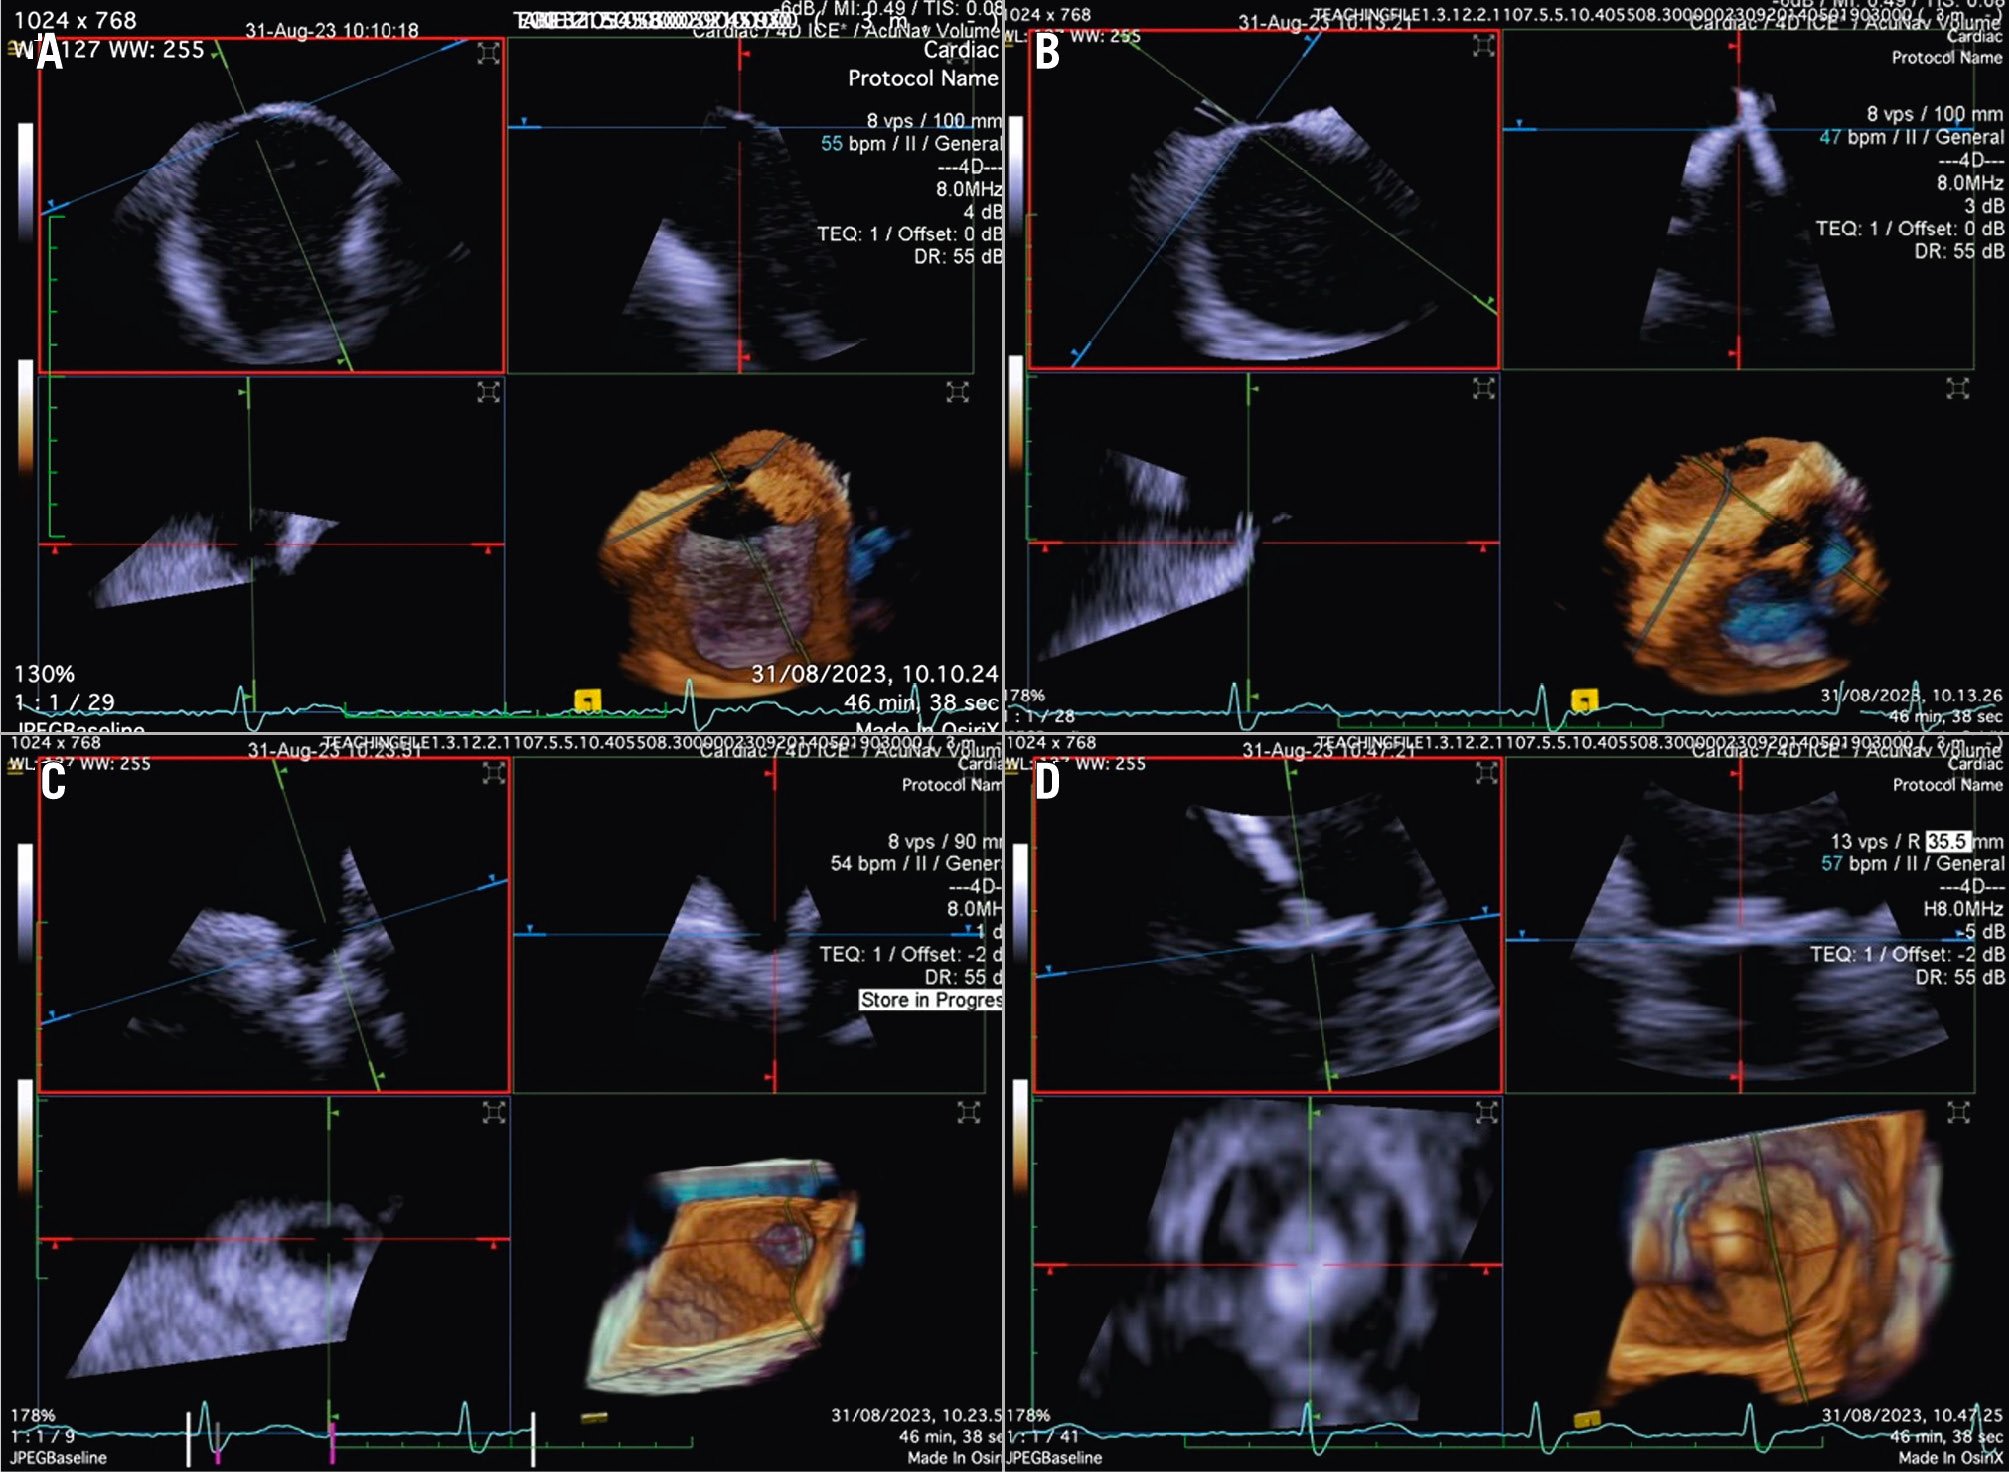

Although PFO/ASD procedures can be performed using a simple 2D ICE probe, in some more challenging anatomical settings (e.g., floppy interatrial septum [IAS], doubt about PFO/small ASD, particular PFO tunnel), 3D ICE can be of added value. When 3D ICE is used for PFO or ASD procedures, positioning within the right atrium is sufficient. With 3D ICE, the septal defect can be visualised in a 3D volume and typically only a catheter position is needed. When starting the procedure, the operator should screen patients for additional septal defects that may have been missed on the preprocedural imaging and determine whether there is a floppy interatrial septum (for PFO) and a sufficient superior and inferior rim (for ASD). Three-dimensional ICE allows us to determine the size of the septal defect (especially for an ASD closure), guide occluder deployment, verify placement post-deployment, and screen for residual shunts1 (Figure 12, Figure 13, Moving image 18-Moving image 19-Moving image 20-Moving image 21-Moving image 22).

Figure 12. Three-dimensional ICE-guided patent foramen ovale closure. A) 2D imaging allowing assessment of needle tenting in the middle of the fossa ovalis. B) Biplane imaging allowing assessment of the catheter after crossing the septum in the superior-inferior and anterior-posterior positions simultaneously. C) 3D multiplanar reconstruction (MPR) allowing assessment of the catheter after crossing the septum. D) 2D imaging showing the deployment of the right disc of the device. E) 3D MPR allowing simultaneous assessment in the lateral, axial, and azimuthal planes of the right disc of the device. F) 3D reconstruction of the device. 2D: two-dimensional; 3D: three-dimensional; ICE: intracardiac echocardiography

Figure 13. Three-dimensional multiplanar reconstruction views of the device in the interatrial septum.